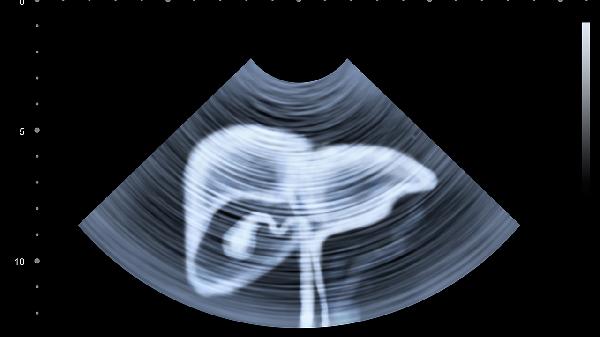

运动时腹压增高可使隐匿性腹股沟疝突出,表现为左下腹坠胀痛,平卧后包块还纳则疼痛消失。需通过超声检查确诊,避免举重等增加腹压的运动,必要时行疝修补术。突发剧烈疼痛伴呕吐需警惕嵌顿疝急诊可能。